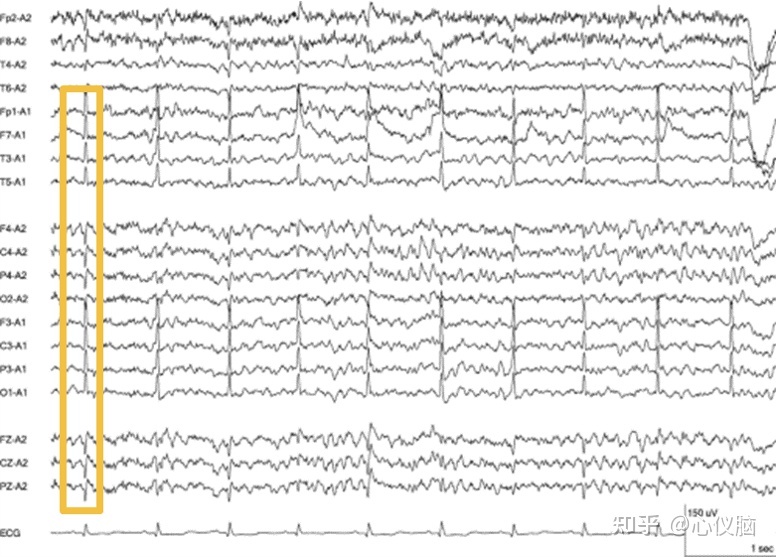

3.心电伪迹

心脏收缩伴随心电图扩展到头部,呈现出的一种有规律且与心跳一致的棘波,常见于颞部导联和耳垂无关电极,主要是由于耳垂参考电极接触不良或参考电极靠近心脏导致。